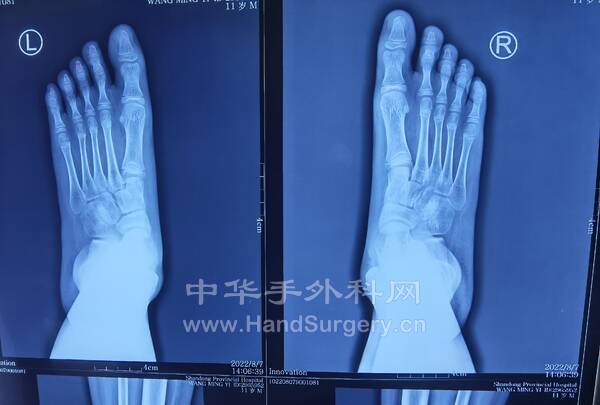

11岁男孩,双足扁平足,在老师这里见过的比较严重的孩子,老师建议手术治疗!

IMG_20220807_152904.jpg

IMG_20220807_152839.jpg

IMG_20220807_112458.jpg

IMG_20220807_152910.jpg